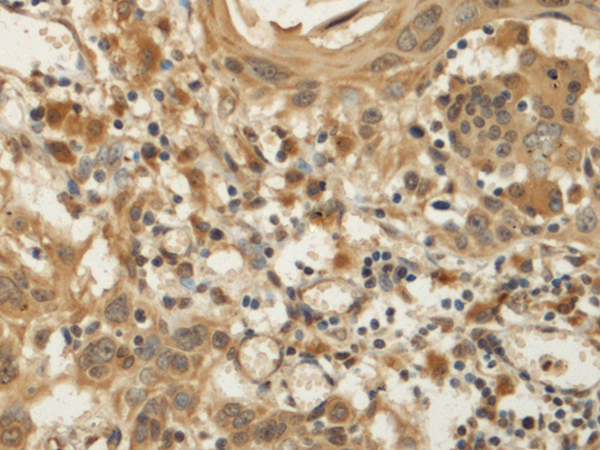

The image is immunohistochemistry of paraffin-embedded Human tonsil tissue using (KATNA1 Antibody) at dilution 1/170.

The image is immunohistochemistry of paraffin-embedded Human esophagus cancer tissue using (KATNA1 Antibody) at dilution 1/170.